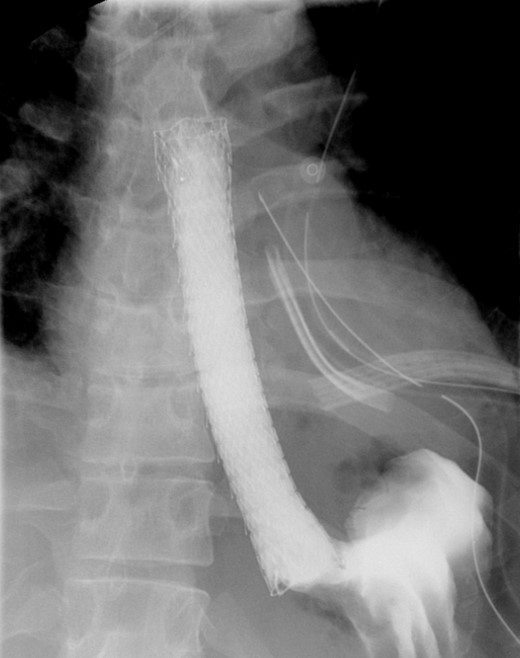

A computed tomographic scan revealed air and fluid surrounding the esophagus (Fig. 1). Esophagogram performed with water-soluble contrast media showed a distal esophageal perforation with a free leak into a large mediastinal cavity to the left of the esophagus (Fig. 2). The patient was triaged directly to the operation room. A left chest tube was placed with improvement in his oxygenation, and grossly murky fluid was drained. Esophagogastroduodenoscopy (EGD) was performed next and revealed a very small caliber esophagus with concentric ringed appearance. A tight stricture was noted in the mid-esophagus, which only allowed passage of a pediatric gastroscope. In the lower esophagus, a 2-cm tear with necrotic edges was visualized 3 cm above the gastroesophageal (GE) junction. With this diffusely strictured and very diseased appearance of the esophagus, the decision was made to proceed with stent placement and thoracoscopic drainage of the mediastinum rather than primary surgical repair via thoracotomy. A fully covered, 15 cm × 19 mm, EndoMAXX® esophageal stent was successfully placed covering the perforation site. Mediastinal washout and drainage was performed subsequently via left thoracoscopy. A postoperative esophagram showed no leak and the patient was started on a liquid diet that was tolerated well. His hospital stay was uneventful, and he was discharged on twice daily high-dose proton pump inhibitor (PPI) on post-operative Day 5. He was placed on a mechanical soft diet on discharge. Repeat upper GI study with water soluble contrast postoperatively showed no evidence extravasation. (Fig. 3)

Shows metallic expandable stent in a satisfactory position in the mid to lower thoracic esophagus extending to the GE junction. Water-soluble contrast is seen filling the stent with no evidence of extravasation.